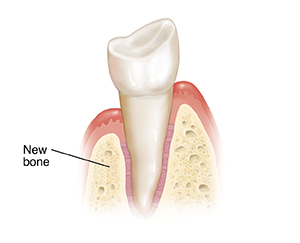

After the area heals. Stitches dissolve or are removed. Though the gum has healed, it takes a year or more for new bone growth to fill the space. Good oral hygiene and regular dental visits are needed to maintain the health of the gums.

| After the area heals. |